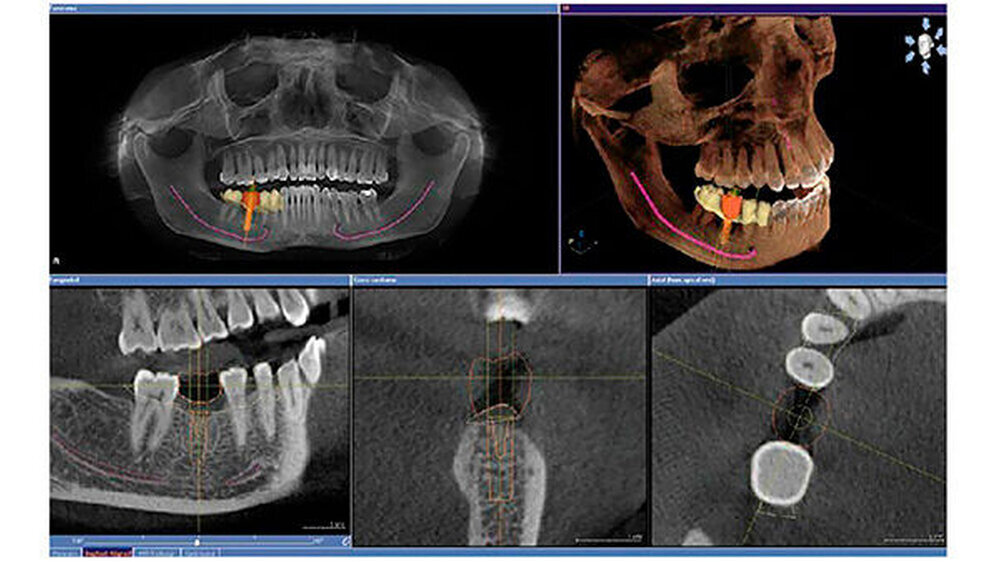

Die Investition in einen digitalen Volumentomografen liegt mit rund 70.000 Euro etwa doppelt so hoch wie bei Top-2-D-Geräten. Die Aufnahmen erleichtern fast jede Diagnose oder Behandlung - von der Wurzelspitzenresektion über den lokalen Knochenaufbau bis hin zum Sinuslift. Fortgeschrittene Systeme schaffen auch die Anbindung an die geführte Chirurgie (Bohrschablonen), teilweise sogar ohne die Notwendigkeit von Abdrücken oder Gipsmodellen. Dadurch wird die Entwicklung von einer primär am Knochenangebot orientierten zu einer von der Prothetik her geplanten implantologischen Behandlung befördert.

Im „digitalen Extremfall“ reichen eine Aufnahme mit dem Intraoralscanner, ein daraus abgeleitetes CAD-Design und dessen Überlagerung mit 3-D-Röntgen-Daten. Auf der Grundlage dieses Inputs kann der Behandler zum Beispiel eine Implantatplanung ganzheitlich angehen, das heißt Knochenangebot und Prothetik am Bildschirm gleichzeitig optimieren. Selbst das gewünschte Emergenzprofil kann dabei schon berücksichtigt werden.

Bei der vorstehend skizzierten volldigitalen Herangehensweise ist nicht einmal eine Röntgenschablone nötig. Klassischerweise muss sie im Labor aus einer konventionellen Abformung hergeleitet werden - über das Meistermodell, eine Wachsaufstellung, eine Tiefziehschiene mit dem prothetischen Vorschlag, montiert auf eine Aufbissplatte. Erst dann erfolgen das 3-D-Röntgen und die eigentliche Implantatplanung.

Für jeden dieser Prozesse stehen heute mehrere Wege zur Bohrschablone offen. Einer davon führt über zentrale Dienstleister: Der Zahnarzt schickt seine Planungsdaten und die 3-D-Röntgenaufnahme dorthin und bekommt nach einigen Tagen die entsprechende Bohrschablone retour. Alternativ dazu kann sie über eine praxis- oder laborseitige Schleifeinheit im eigenen Hause und ohne Zeitverzögerung hergestellt werden.Die höherwertigen 3-D-Systeme, im hohen fünfstelligen oder sechsstelligen Euro-Bereich, weisen einen größeren Scan-Bereich auf. Dies öffnet die Tür zu Ganzkieferaufnahmen inklusive Kiefergelenk - ideal bei Kieferfrakturen, bei Dysgnathien oder bei der Behandlung der craniomandibulären Dysfunktion.